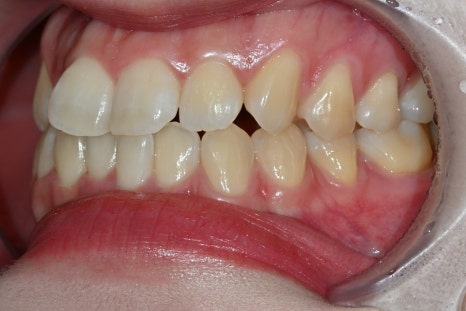

A design that also considers the gums

In this case, gingival contouring was performed together for a more natural result.

Laminate should

not only look at the teeth,

but also at the gum line

in order to look natural.

At Seoul Ob Dental Hospital, we design while considering the overall balance, including the ratio between the teeth and gums.